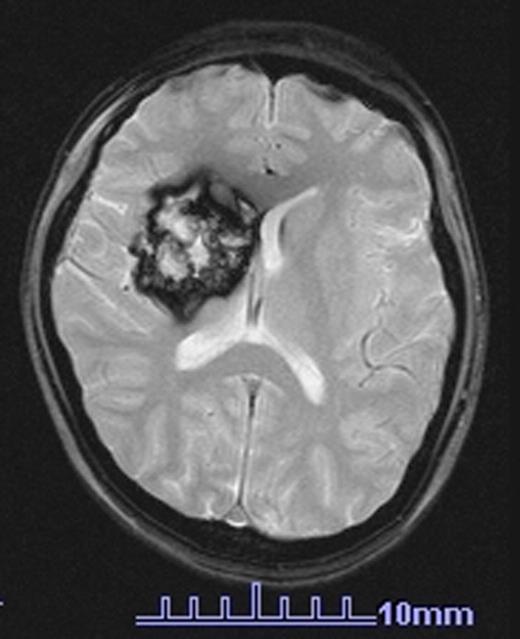

Twenty-five patients (37.9%) was diagnosed RICH. The age at the time of the diagnosis was 11-40 years old (median 27 years old). The age at the time of BMT was 1-22 years old (median 9 years old). The period from BMT to diagnosis was 10-24 years (median 16 years). All cases received TBI as conditioning of BMT and/or cranial radiation (CR) prior to BMT as treatment of primary disease. RICH was found in 25/48 (52%) who received TBI and/or CR, and was not found in any of 18 patients without radiation therapy to the brain. Total dose to the brain was 10-36 Gy. Clinical manifestations were present only in four cases. RICH SCORE ranged 1-18 points (median 4 points). Small RICHs tended to be recognized only by T2* weighted image, but not by routine imaging methods. Classification of the severity was mild in 13 patients, moderate in 8 patients and severe in 4 patients. Severity was correlated with higher radiation dose and/or with younger ages at transplantation. RICH SCORE increased yearly in 7 of 25 patients. One case developed giant RICH more than 40mm as shown in the attached image.